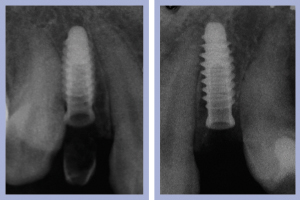

- Figg. 20a, b, c – Controllo clinico e radiologico a 2 settimane dall’intervento

- Fig. 20b,c

- Figg. 29a, b Manufatti di destra e radiografia di controllo. Si noti l’ottima integrazione tissutale

- Figg. 30a, b – Manufatti di sinistra e radiografia di controllo